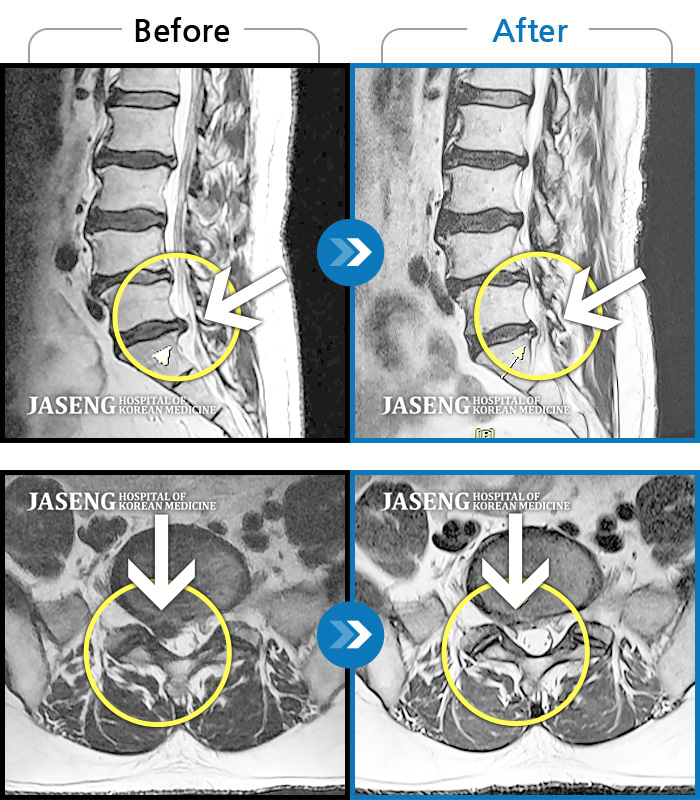

허리디스크

도움받은 사례

광주 · 장영우 원장

양측 허리의 묵직한 통증 및 기침 시 증상이 심화되어 내원하셨습니다.

촬영시기

2024.12.09 ~ 2025.05.24

2025.06.05

조회수 238